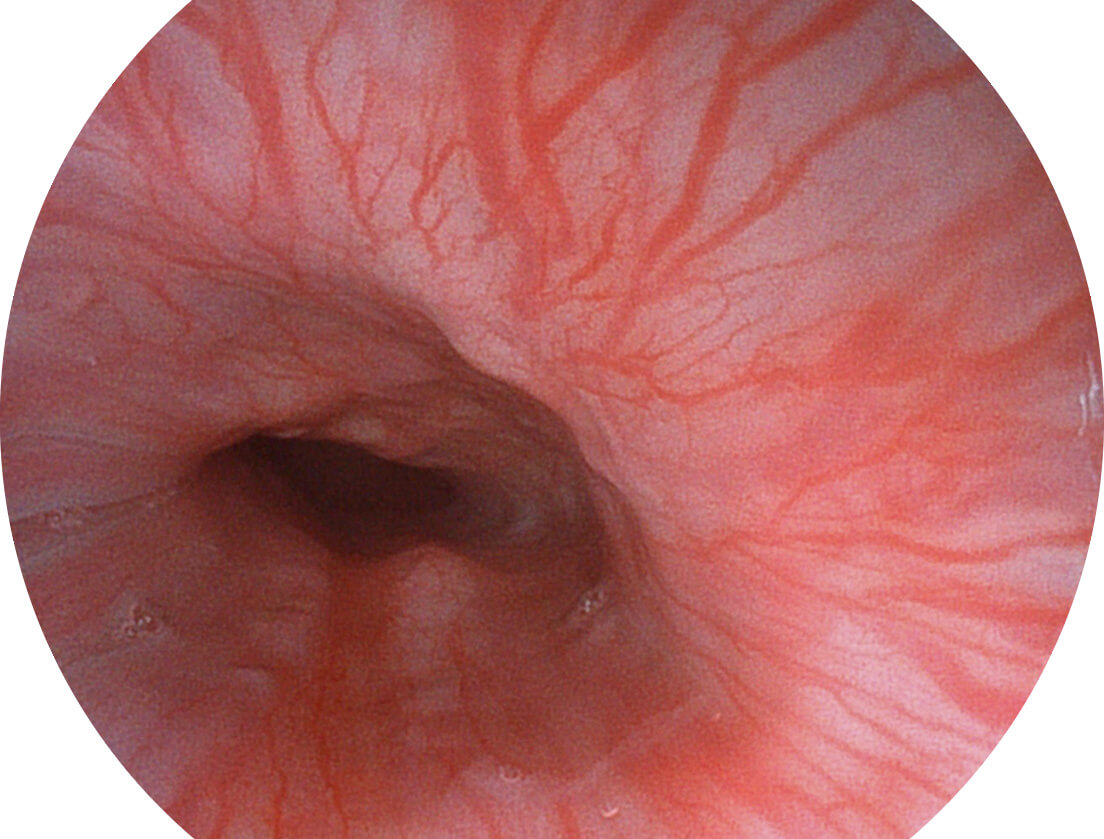

白光图像